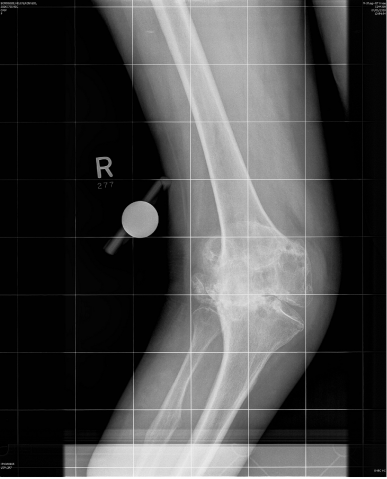

A 76 year old woman presented with a painful, valgus right knee which had progressively worsened over past 2 years. On clinical examination she had a marked valgus deformity of her right knee measuring 49° using a goniometer. Range of motion on examination was measured to be 5° to 100° with an extensor lag of 15°; the valgus deformity was not correctable on clinical examination. Radiographs confirmed a massive valgus deformity of the right knee with a bony defect in the lateral femoral condyle and lateral tibial plateau (Figure 1–3). The patient was consented to have a simultaneous peri-articular femoral osteotomy and total knee arthroplasty procedure in order to address the severe valgus deformity and osteoarthritis. The patient was informed that the data concerning her case would be submitted for publication and an informed consent obtained. Pre and post operative WOMAC and VAS scores were obtained.

Figure 1 Preoperative AP view of the knee.

Figure 2 Preoperative lateral view of the knee.

Figure 3 Preoperative PFJ view of the knee.